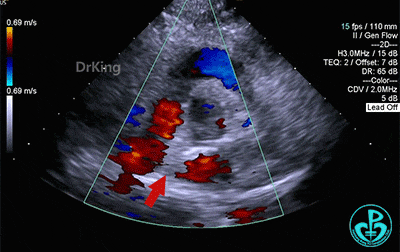

房间隔中部有回声中断,测ASD大小:8×8×9mm,CDFI探及左向右分流,距主动脉根部0mm,距二尖瓣环10mm,距房顶14mm,距上腔静脉13mm,距下腔静脉11mm。

主动脉短轴切面下观察,封堵器位置正确呈Y字形抱住主动脉根部,形态良好,未见残余分流。

完全释放后超声观察封堵器形态良好,未见分流,封堵成功。